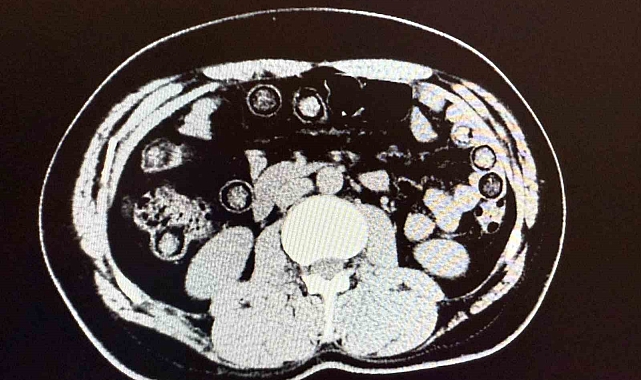

Muş Valiliği tarafından yapılan açıklamada, "Narkotik Suçlarla Mücadele Şube Müdürlüğümüzce uyuşturucu madde sevkiyatına engel olmak için yapılan çalışmalar neticesinde İran uyruklu 2 şahsın şehirlerarası yolcu otobüsü ile illere uyuşturucu madde nakli gerçekleştirebilecekleri değerlendirilmiş, 6 Aralık günü saat 11.30 sıralarında şüpheli şahısların görevlilerimizce yapılan sorgulamasında uyuşturucu madde naklettikleri yönünde kuvvetli şüphe oluşmuştur. Hastanede yapılan iç beden muayeneleri sırasında çekilen tomografi görüntülerine göre uyuşturucu madde yuttukları tespit edilmiştir. Hastanede yapılan tespit sonrasında şahısların midelerinde toplam 94 adet kapsül içerisinde daralı ağırlıkları 928 gram gelen metamfetamin maddesi ele geçirilmiştir. Şüpheli şahıslar hakkında 'uyuşturucu ve uyarıcı madde ticareti' suçundan işlem yapılmak üzere Cumhuriyet Başsavcılığına intikal ettirilmiş ve çıkarıldıkları mahkemece tutuklanmışlardır" denildi.